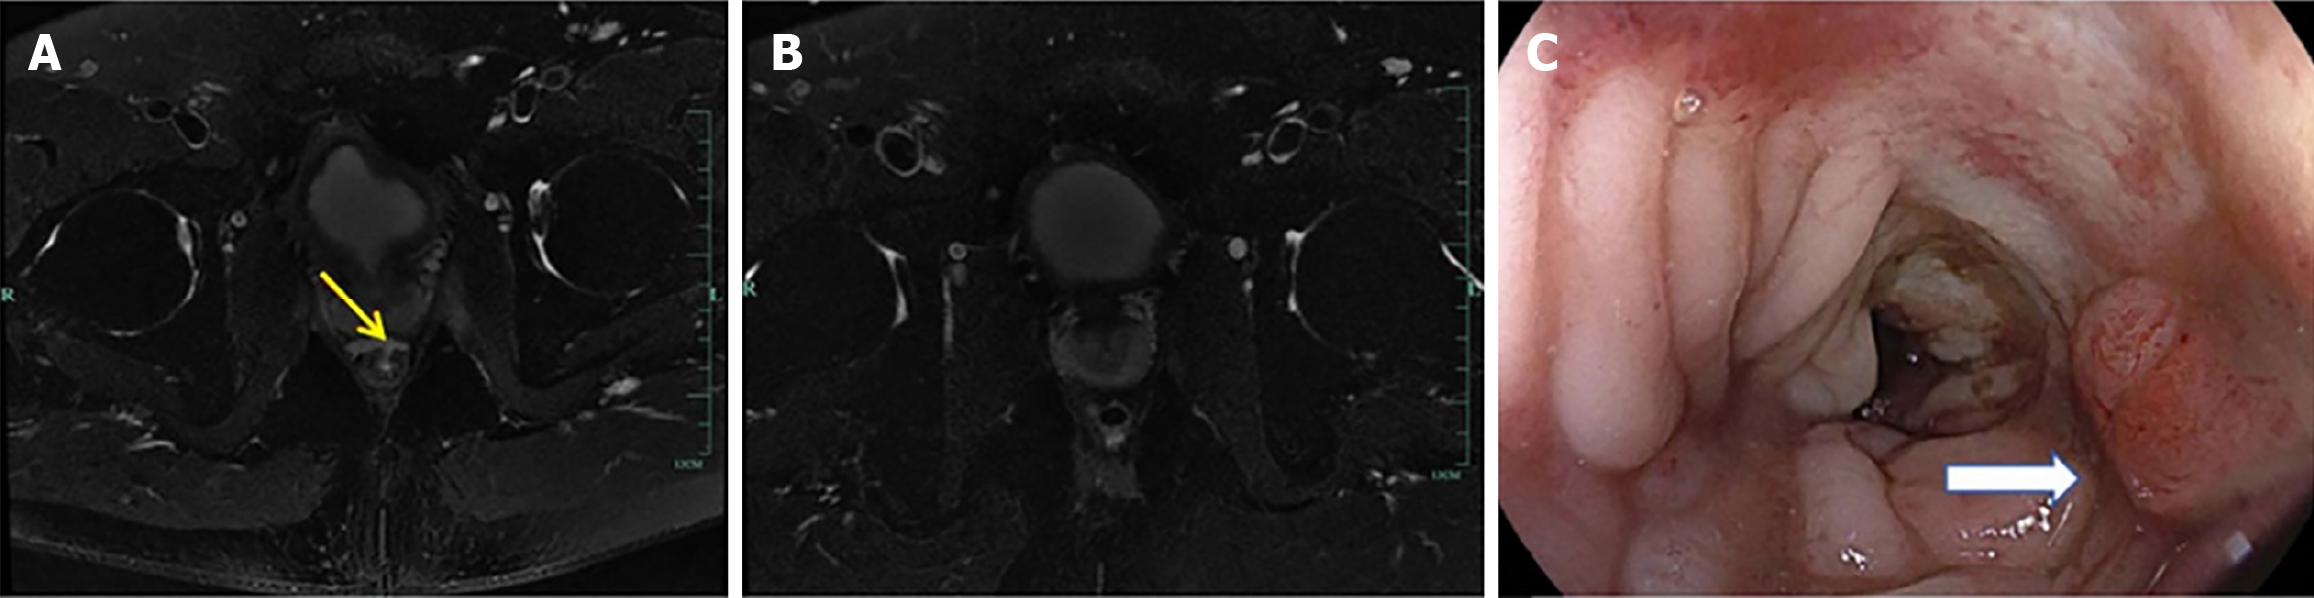

Case 2: Abdominal CT scan revealed a discontinuous anastomosis on the left rectal wall (Figure 3A). A follow-up CT scan post-treatment demonstrated a continuous anastomosis with no evident gap (Figure 3B). Subsequently, colonoscopy confirmed that the fistula had substantially healed (Figure 3C).